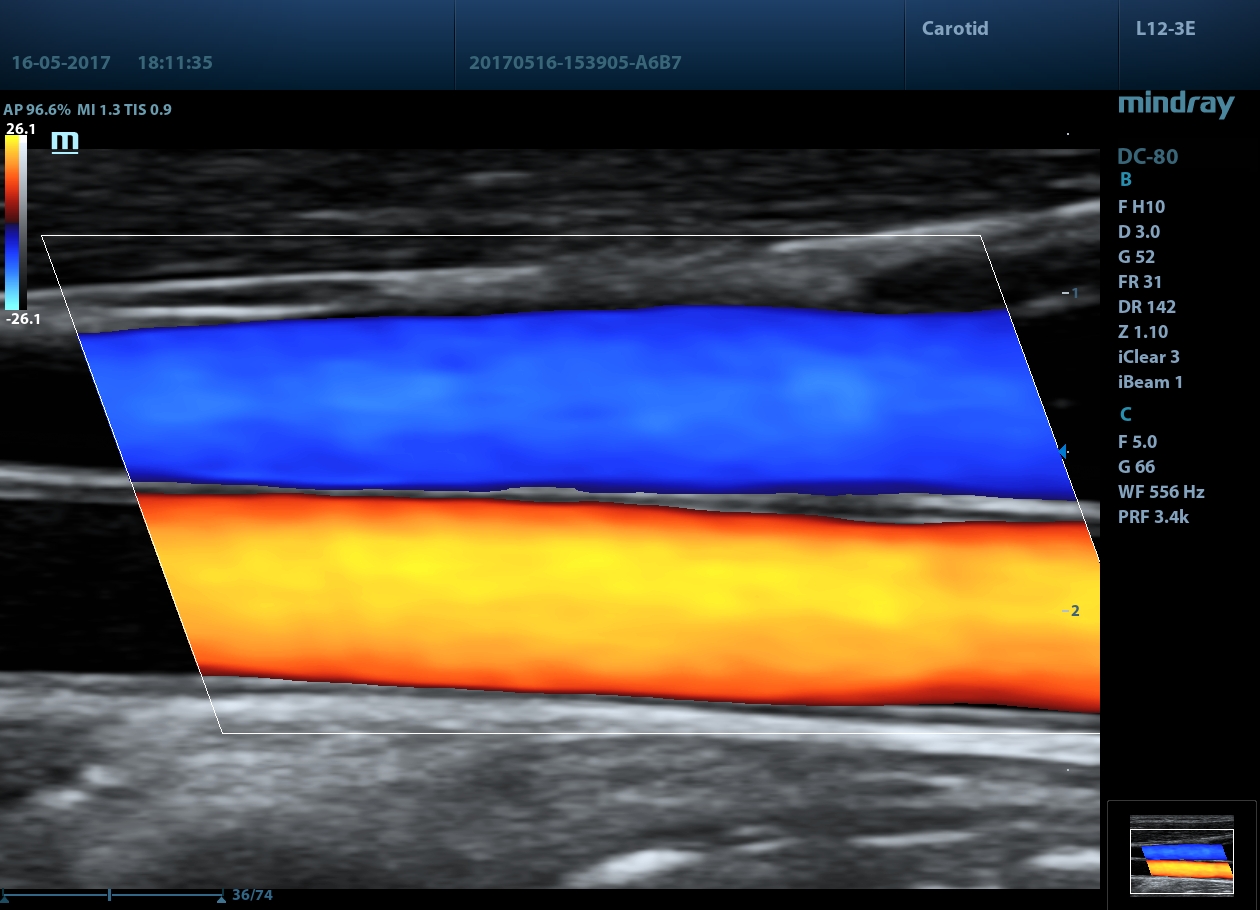

DC-80 X-insight

![]() Thunder-speed imaging with X-Engine(CPU+GPU)

X-Engine(CPU+GPU)에 의한 초고속 화상처리의 새로운 X-Engine은 GPU와 CPU 를 내장하고 있기 때문에 멀티코어의 병렬처리가 가능하고, 고속의 화상처리와 뛰어난 선명도를 실현합니다. 고도의이미징엔진으로 기존보다 3~4배 속도로 이미징 속도가 빨라지고 3D/4D 등의 애플리케이션을 통해 매우 빠르고 선명한 이미지를 보여줍니다.